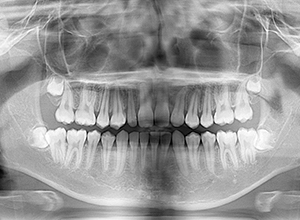

X-Ray

パノラマ所見 上下顎第三大臼歯は埋伏歯しており、上顎右側犬歯は先天欠如をしていた。

批評・予后 側貌はconcave typeであり、下顎歯列は叢生が少ないこと、右上3欠損、左右上2は矮小歯であることを考慮して右上C、左側2抜歯とした。治療後はアンテリアレシオの調和を図るべく右上2は暫間的修復(CR)にて歯冠幅径を大きくしている。保定終了後には同部位は最終補綴を装着する予定である。